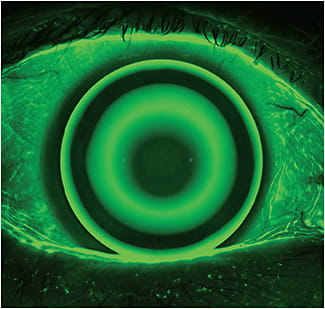

ORTHOKERATOLOGY

Orthokeratology (ortho-k) has been used as a method to correct myopia for more than 50 years. In recent years, growing evidence indicates that ortho-k can successfully slow the rate of progression of myopia.27-30 With the introduction of reverse geometry lens designs and high permeability materials, ortho-k has become a very popular myopia management option. The myopia control effect is similar to soft multifocal lenses, with 30% to 80% slowing of axial elongation.27,28 Ortho-k effectively eliminates the refractive error, such that no correction needs to be worn during the day. Toric ortho-k lenses are available for patients who have significant amounts of astigmatism.31